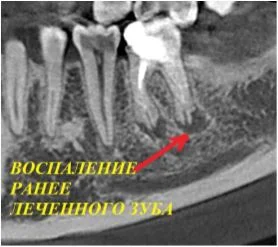

Компьютерная томография - это ключевой метод обследования в имплантологии

Воссоздавая орган (зуб) или даже совокупность органов, необходимо предельно точно знать исходную ситуацию. Корни зубов, каналы зубов, крупные сосудисто-нервные пучки, идущие внутри костной ткани, верхнечелюстная пазуха во всех подробностях и т.д. - в неискаженном виде все это можно увидеть только на компьютерной томограмме. Стоит ли говорить, что все эти структуры важны для имплантации, так как могут быть легко поврежденфы в ходе операции.

Как получить гарантированный результат имплантации? При помощи компьютерной томографии!